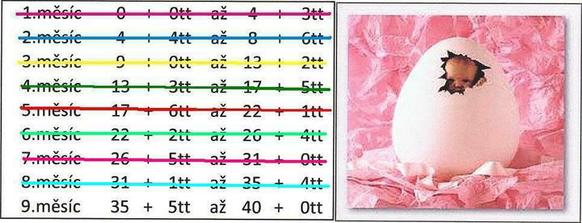

čeká nás ve 20 týdnu velký utz (doufám že nám potvrdí Terezku, mám už nějaké růžové věcičky🙂) a kontrola srdíčka u dětského kardiologa a o týden později poradna